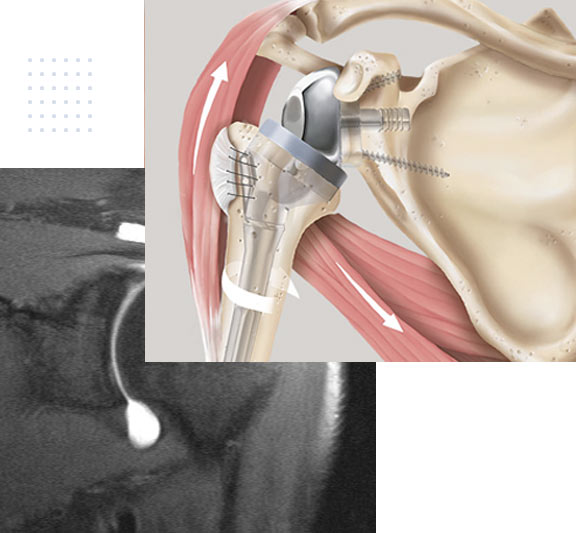

Sehnenrisse an der Schulter

Die Behandlung der Rupturen ist mannigfaltig. Einerseits hängt dies vom funktionellem Anspruch des Patienten ab, andererseits auch von der Qualität der Muskel-/Sehneneinheit.

Sehnenrisse an der Schulter können unfallbedingt zu Schmerzen und Bewegungseinschränkungen führen, können sich aber auch im Verlaufe des Lebens mit zunehmenden Alter ohne äussere Einflüsse entwickeln. Es sind mehrere Faktoren bekannt, die bei Menschen die Chance einer Ruptur erhöhen.